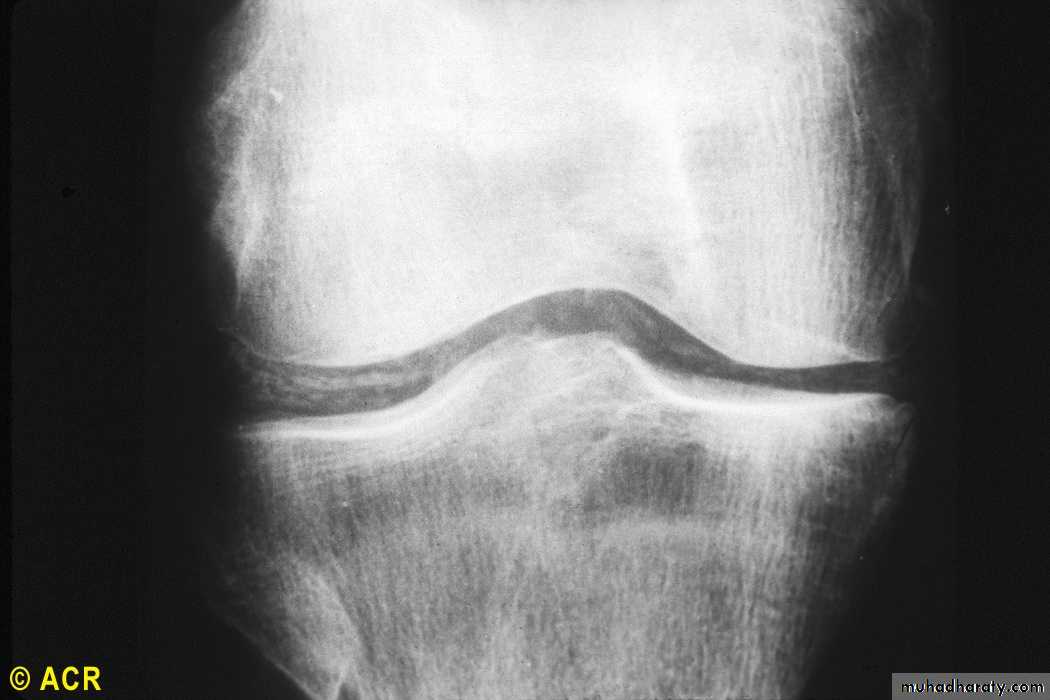

Chondrocalcinosis : knee (radiograph) (pseudogout)